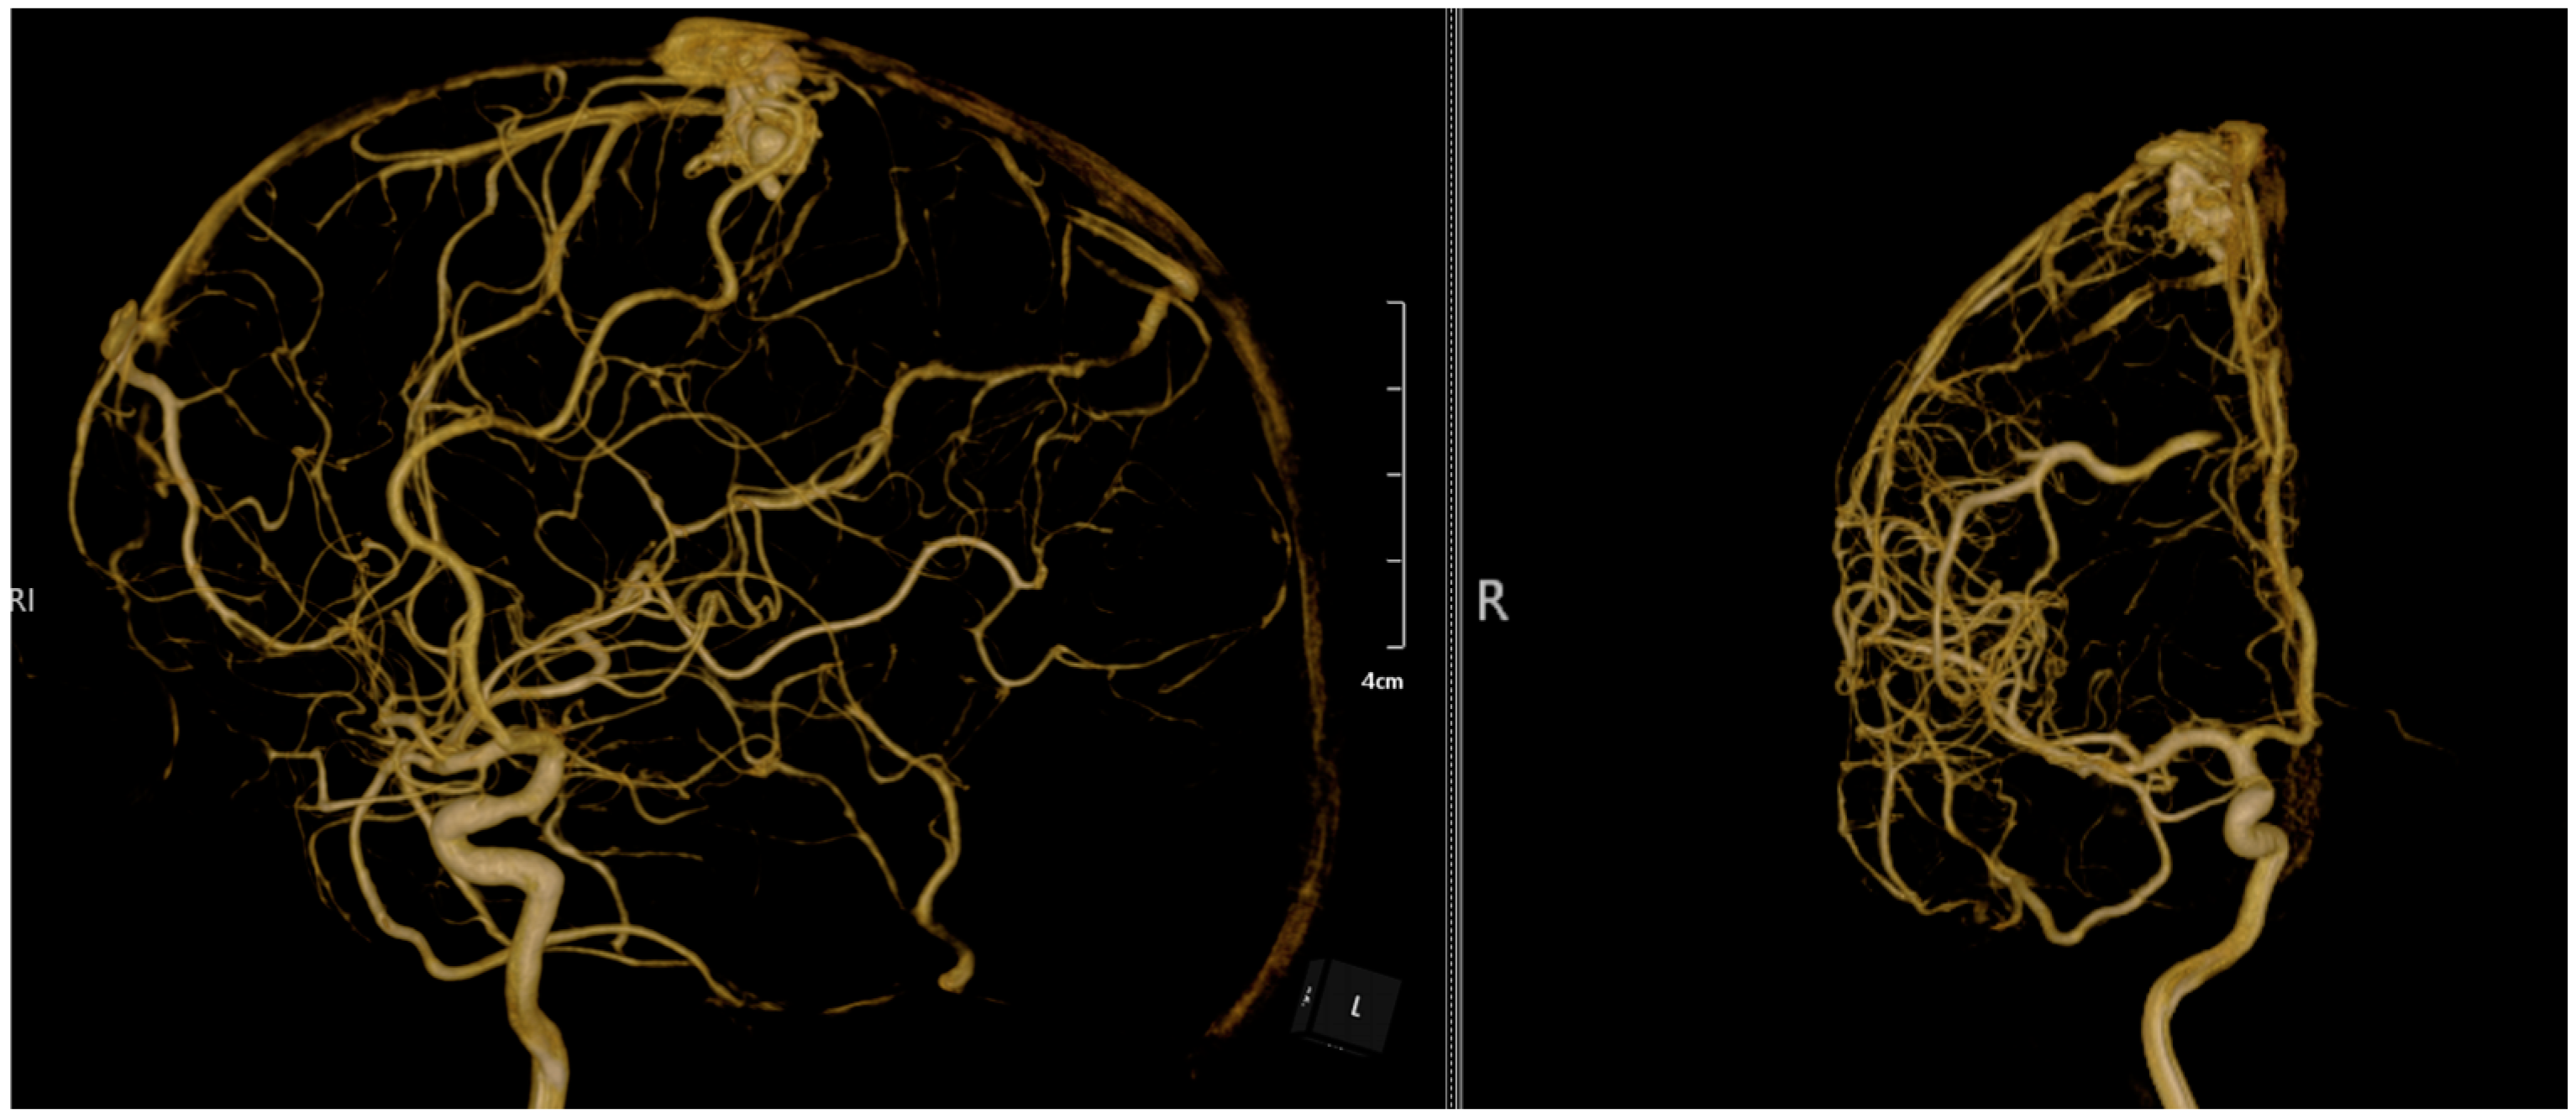

2. Case Presentation